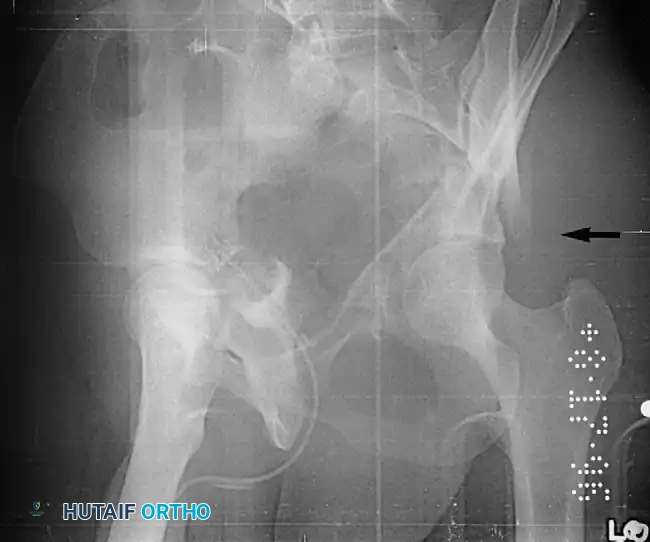

While most acetabular fractures are not surgical emergencies, an irreducible fracture-dislocation of the hip is a notable exception. The historical term "central fracture-dislocation" describes a severe medial subluxation of the femoral head into the true pelvis.

Fig. 53-3 Transverse acetabular fracture with true central fracture-dislocation; intrapelvic femoral head can become locked between superior and inferior fracture fragments.

In these scenarios, the femoral head may become incarcerated between the superior and inferior fracture fragments, rendering closed reduction impossible.

Fig. 53-4 Anteroposterior pelvic radiograph ( A ) and CT scan ( B ) of irreducible hip dislocation with posterior wall acetabular fracture. Posterior wall fragment is incarcerated, blocking reduction.

If closed reduction under conscious sedation or general anesthesia fails, urgent open reduction is mandated. A rapid, fine-cut (2-3 mm) Computed Tomography (CT) scan should be obtained to identify the incarcerating fragment—often a rotated posterior wall fragment or an intra-articular osteochondral loose body. Prolonged dislocation exponentially increases the risk of femoral head osteonecrosis and irreversible sciatic nerve ischemia.